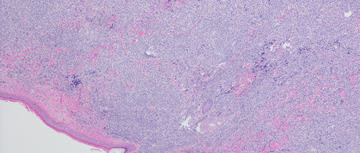

uveal melanoma with unresectable hepatic metastases

Drug Updates

Pharmacist’s Application to Practice: Hepzato Kit™

Lainey Vargo, PharmD, PGY2-Oncology Resident Katie Murto, PharmD, BCOP and Crystal Heise, PharmD, BCOP WVUH Hospitals, Morgantown, West Virginia.